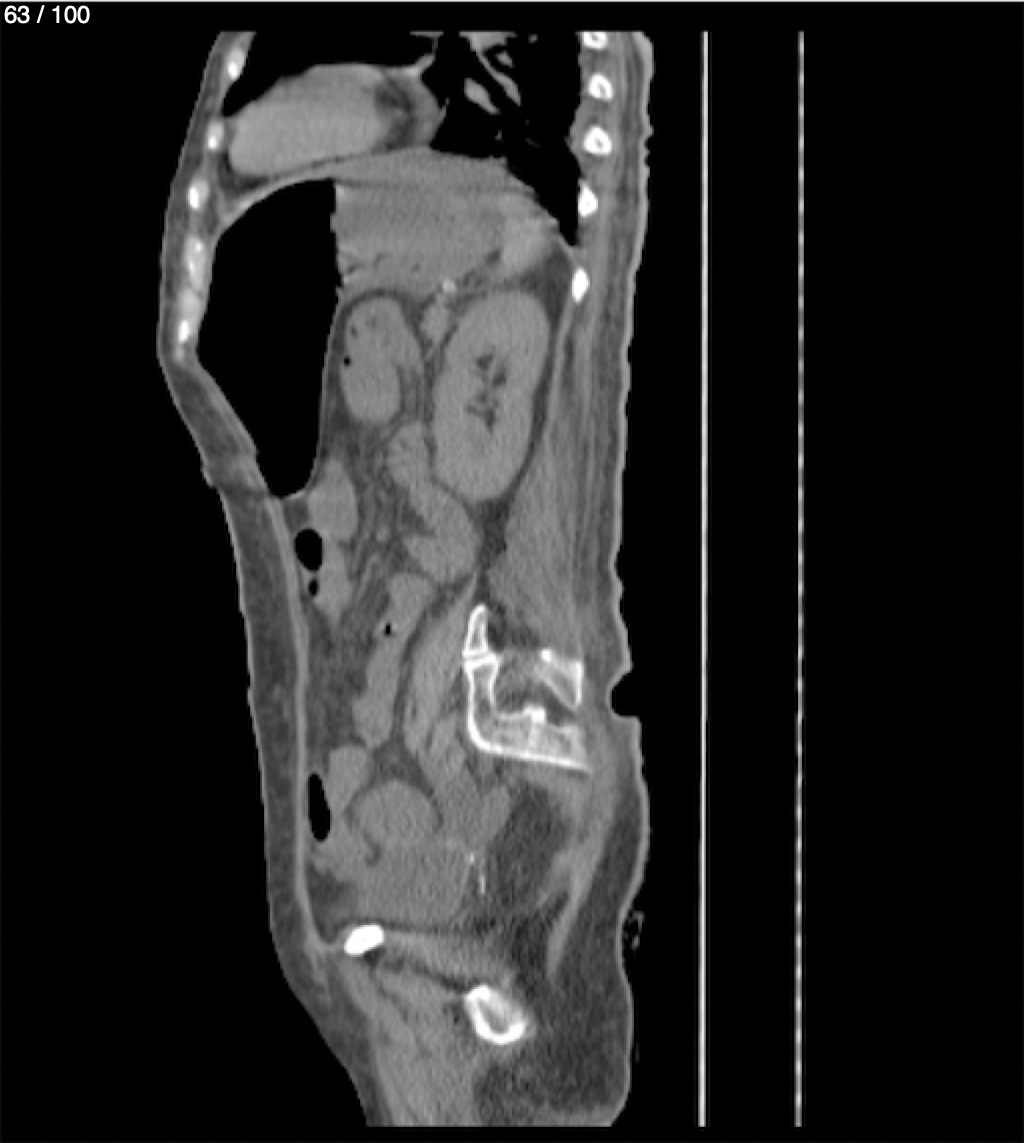

Hilda Geronimo Mendez 60A - T.C Abdomen Simple